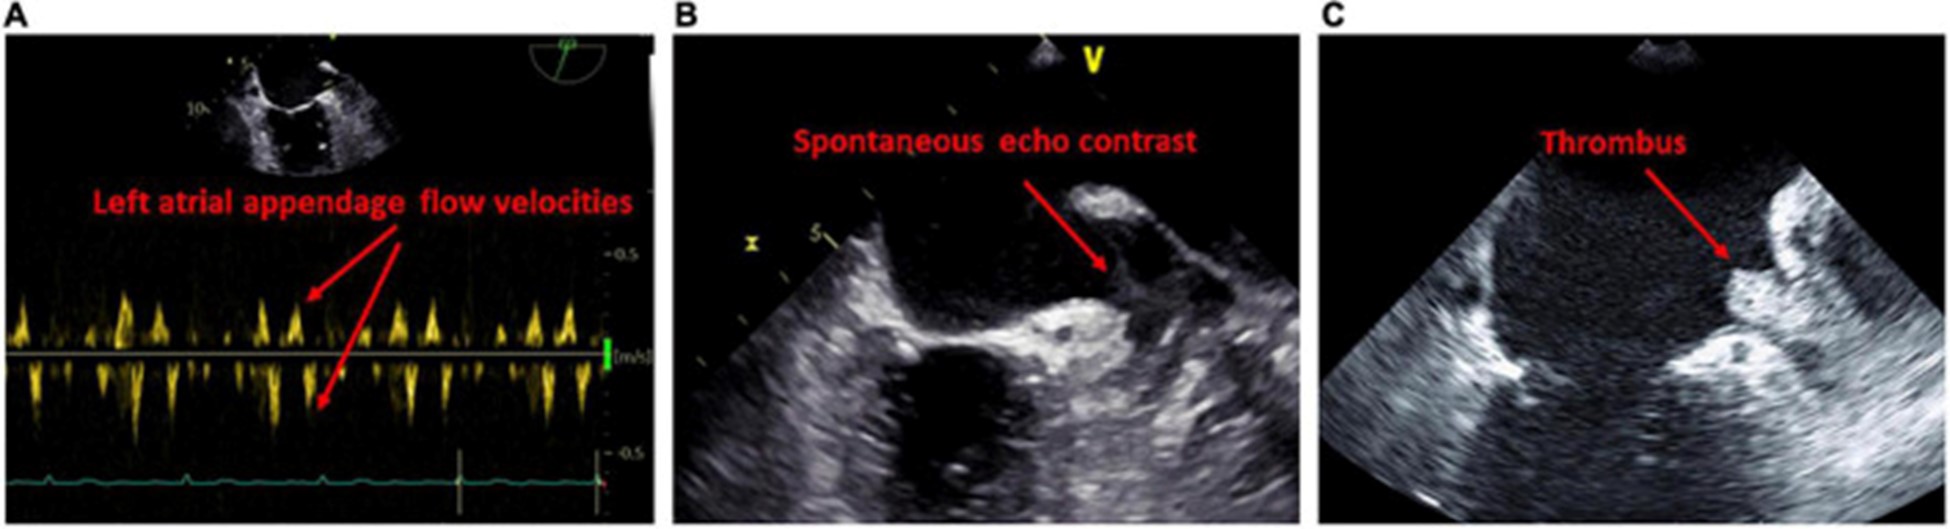

图 4:经食道检查提示左心房心肌病的结果。(A)左心耳口的血流减少。(B)左心耳自发回声对比的证据。(C)左心耳血栓的证据。

经食道超声心动图

经食道超声心动图的一个重要优势是更精确地评估左心耳。关于经食管异常与左心房心肌病相关性的证据有限,LACM 主要通过延迟增强 MRI 确定纤维化来确定。经晚期钆增强 MRI 诊断,与没有血栓的患者相比,有 LA 附肢血栓的患者有更多的 LA 纤维化 。有自发回声对比的患者的 LA 纤维化程度甚至高于没有的患者。此外,高心房纤维化患者更可能在左心耳同时出现血栓和自发回声对比(70)。众所周知,LA/LA 附件血流动力学减少和 LA 大小增加是血栓和自发回声对比发生的危险因素 (图 4)。